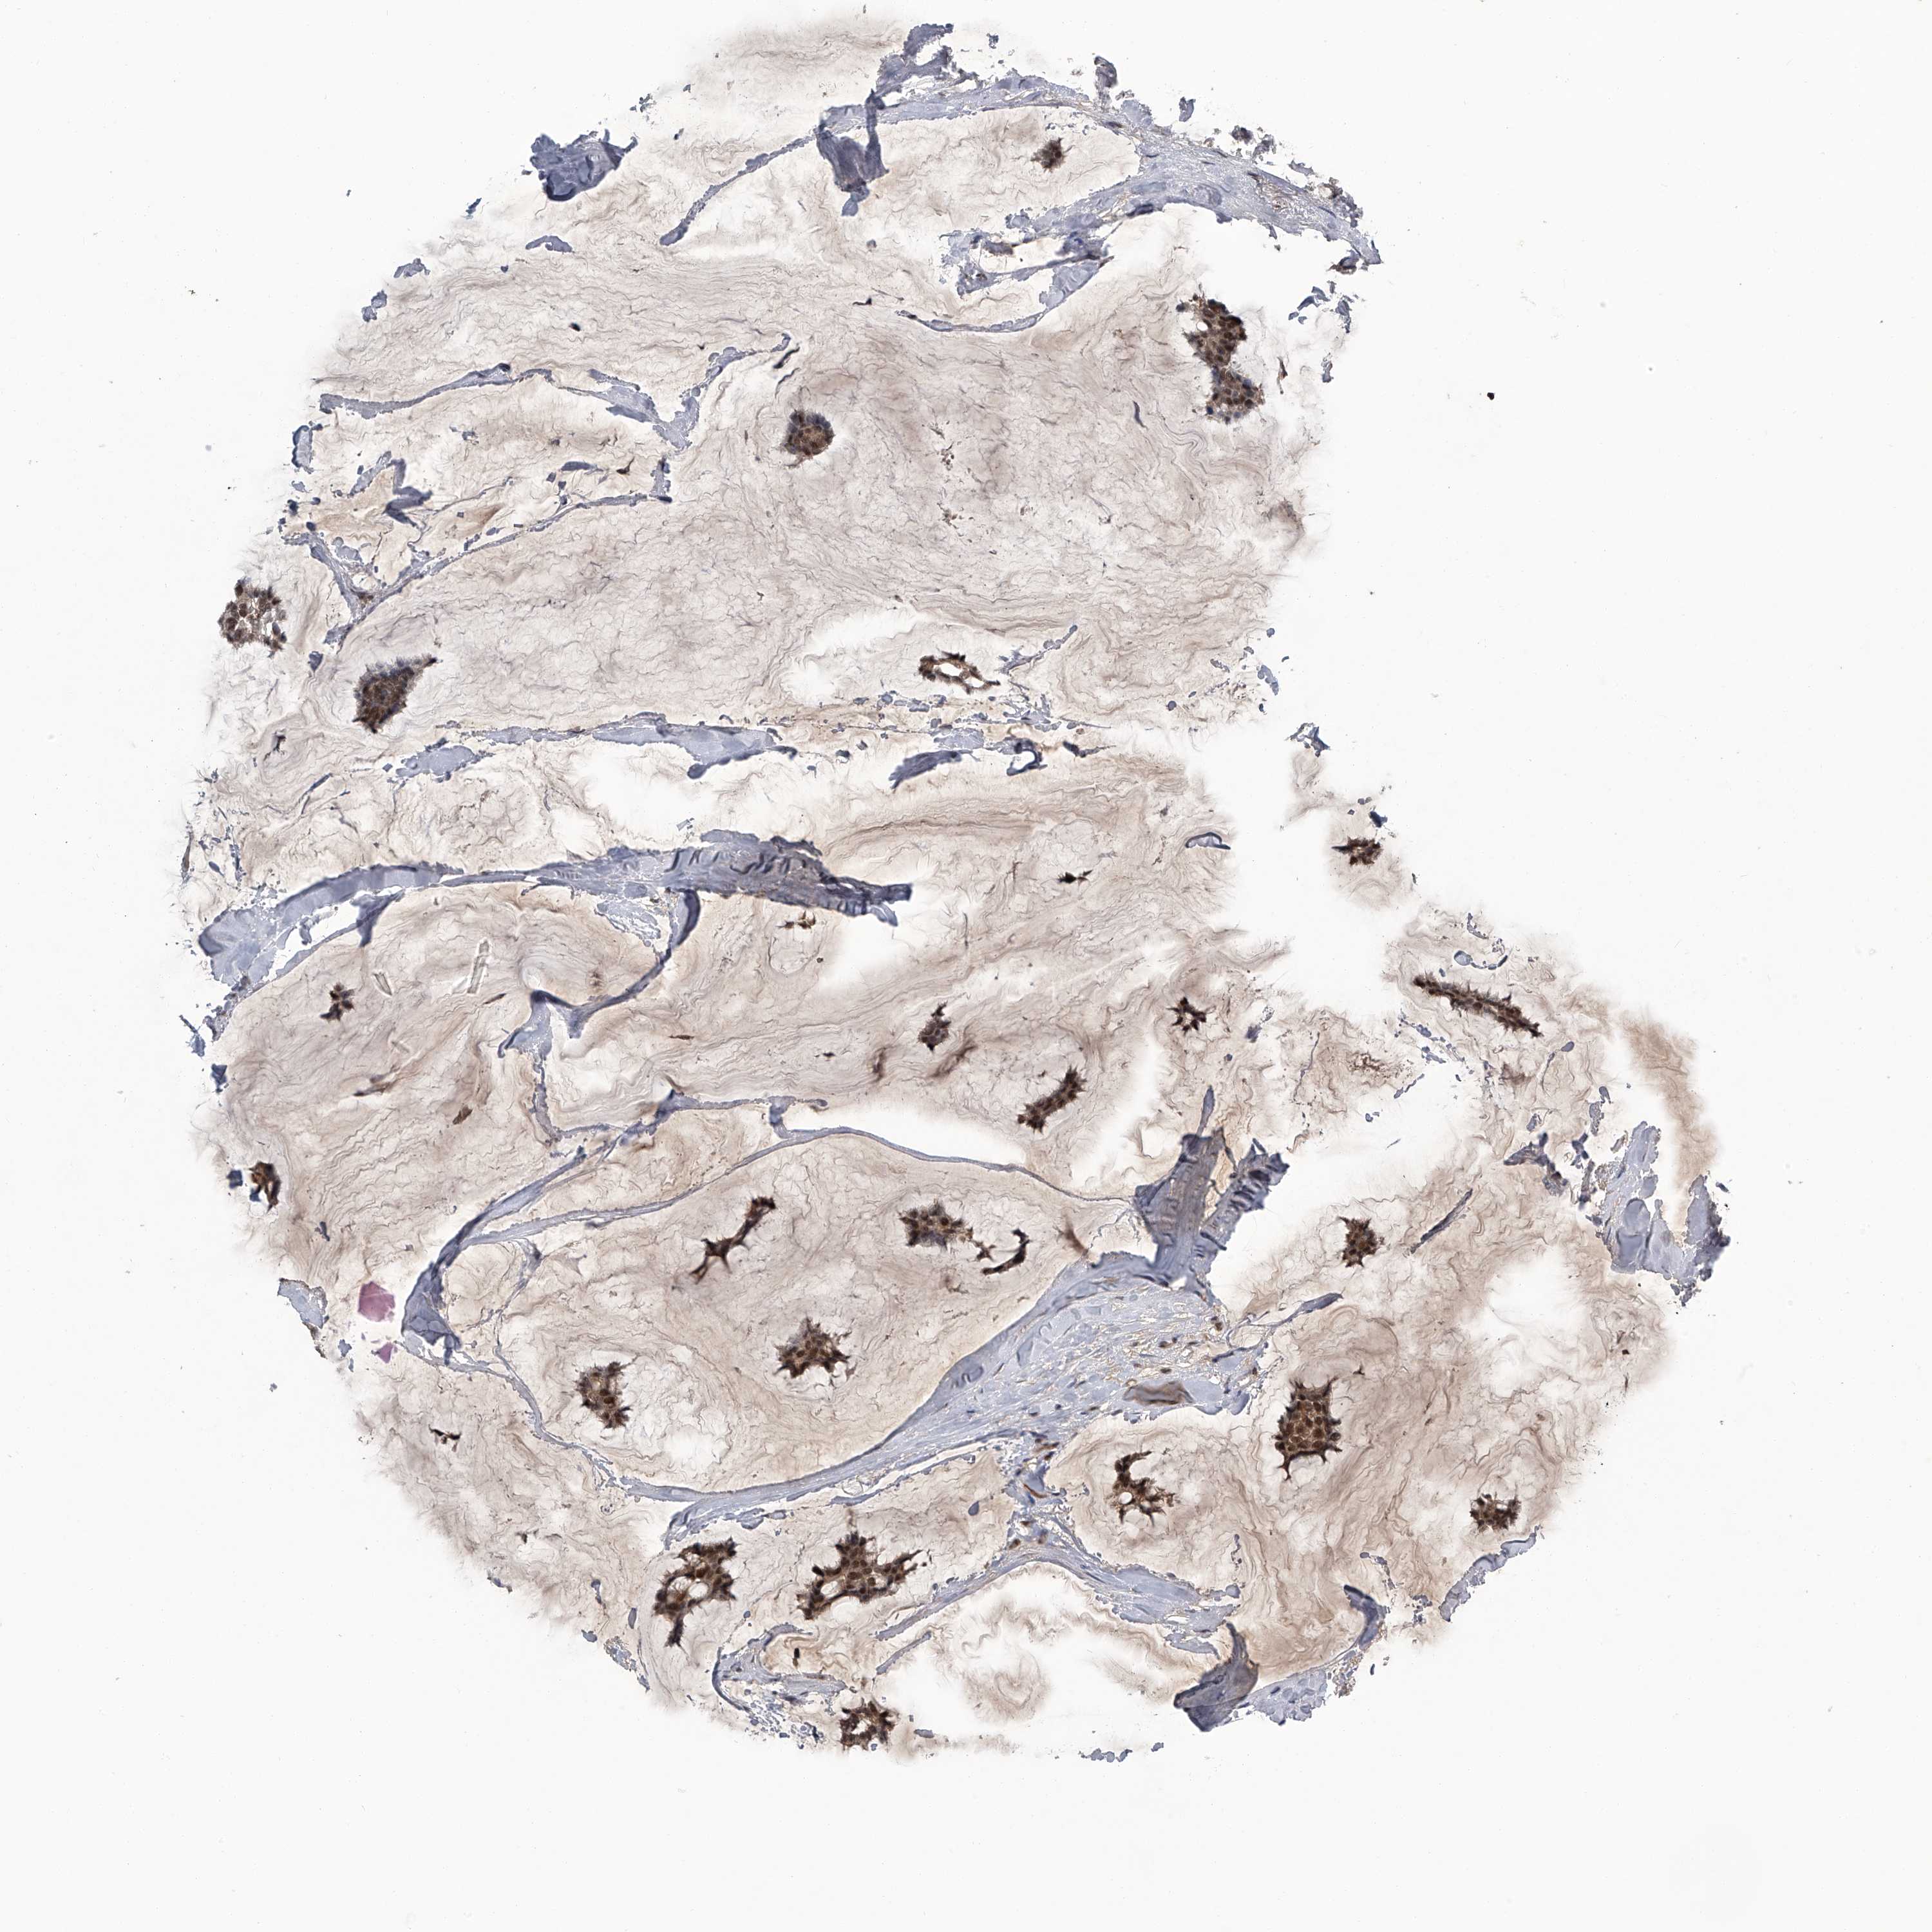

CANCER BREAST CANCER Show tissue menu

BRCA TCGA BRCA VALIDATION PROTEIN EXPRESSION